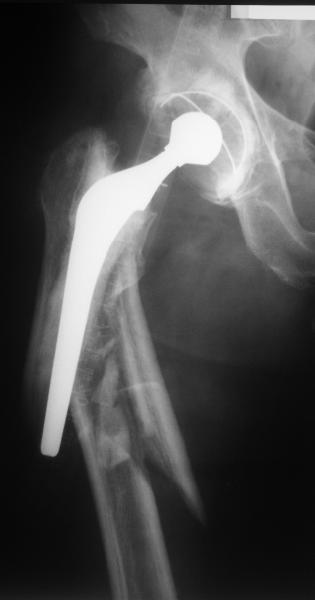

Мужчина 59 лет, переведен к нам через >6 нед после автотравмы, сбит

машиной. 5 лет назад цементное проезирование DePuy Elite+

Как классифицировать этот перелом? Ножка мне кажется стабильной, т.е.

Vancouver B1? Или B2?

Сейчас есть варус и укорочение, ручная  тракция уже не устраняет

смещение.

Как бы Вы вели такого пациента?

Думается про ретроградный гвоздь, который присоединяется к ножке

протеза. Еще не доводилось такого делать на цеметной ножке.

Также, наверно, полезно будет предварительно восстановить длину

аппаратом.